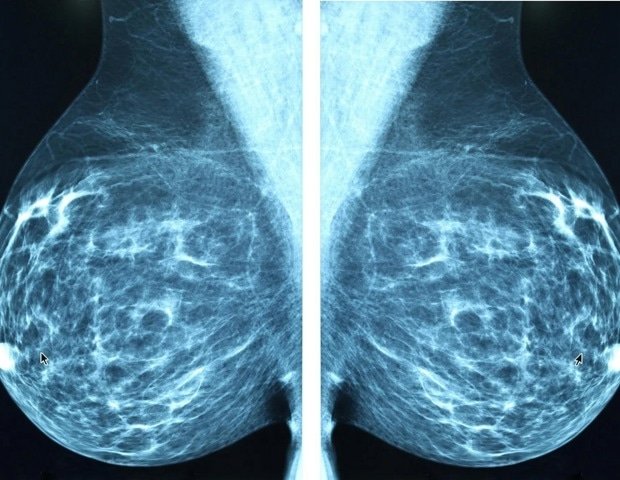

The funding will enable preclinical development of VLX-ADC-001, an ADC targeting LIV-1 for metastatic triple-negative breast cancer (mTNBC), with candidate selection scheduled for June 2026, as well as support GMP compliance and partnership activities for the company’s GoldenSite™ binding platform.